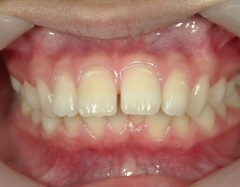

矯正歯科(全顎ワイヤー矯正)治療後

全顎ワイヤー矯正 症例(5)

20歳女性 浜松市東区

在住

治療期間2年4

ヶ月

矯正歯科 治療後